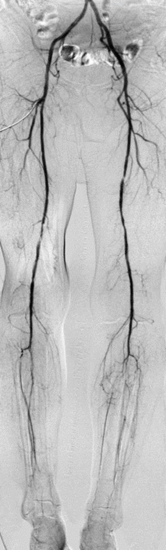

Digitale Subtraktionsangiografie:

Diese Untersuchungsmethode wird nur noch im Rahmen der Therapie oder bei unklaren durch andere Methoden erhobenen Befunden durchgeführt. Dazu wird nach Verabreichung eines Schmerzmittels eine Punktion der Oberschenkel- oder Armarterie durchgeführt und ein dünner Katheter in das Gefäß vorgeschoben. Über diesen Katheter erfolgt eine Kontrastmittelinjektion zur Darstellung der Gefäße. Ein spezielles Röntgengerät macht während der Injektion Aufnahmeserien des Blutflusses in dem zu untersuchenden Gefäßgebiet.